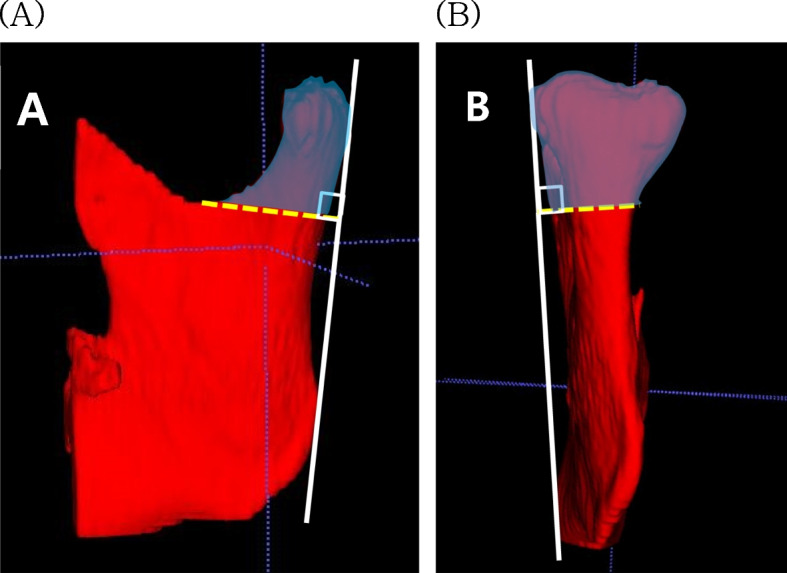

Methods: The study included 16 patients (6 with Class II malocclusion, 10 with Class III malocclusion) who underwent bilateral sagittal split ramus osteotomy at Chonnam National University Hospital. Cone-beam CT data were collected at three specific time points: before surgery, immediately after surgery, and approximately 6 months post-surgery. Mandibular movement was measured using InVivoDental 5.4.6. ITK-SNAP 3.8.0 was used to assessed condylar volume changes post-surgery. Condyle positions were evaluated in four parts with RadiAnt DICOM Viewer 4.6.9. Statistical analyses were performed using the SPSS version 23.

Results: Considering both Class II and III malocclusion, a 2.91% volume reduction was noted immediately and at 6 months after surgery. Both Class II and III cases demonstrated a decrease in superior joint space by -0.59 mm and medial joint space by -1.09 mm. No significant correlation was found between this process and condylar volume change.

Conclusions: The mandibular condyle volume decreased, and superior-medial movement of the condyle was detected in patients with Class II and III malocclusion immediately and at 6 months after surgery with no volume-position correlation.